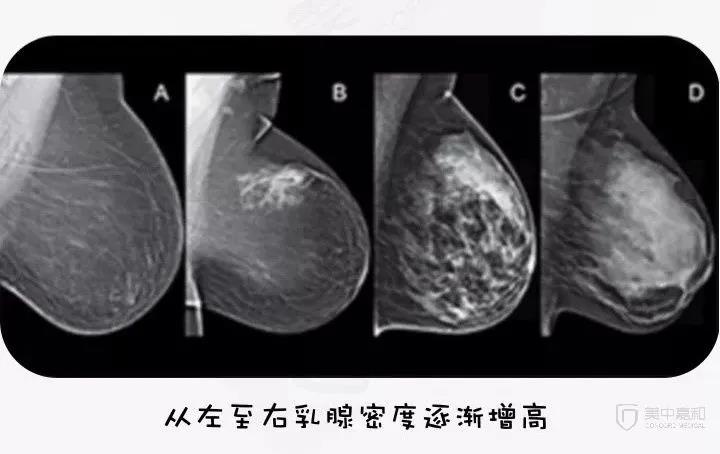

美国放射协会将乳腺分为4型:

脂肪型(乳腺大部分组织为脂肪)

少量腺体型

多量腺体型

致密型(乳腺大部分组织为腺体,非常致密)

最新的研究表明,致密型乳腺相比脂肪型乳腺,具有更高的乳腺癌发病率。